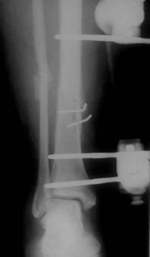

| Trotzdem wurde der Fixateur nach 3 Monaten entfernt. Die Patientin

belastete voll. Einen Monat später kam die Patientin mit einer

sichtbaren Fehlstellung des Unterschenkels wieder. Jetzt war auch

Callus zu sehen. |